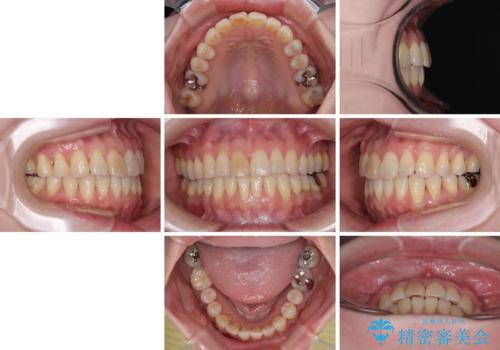

前歯のデコボコをインビザライン・モデレートで矯正治療

- 9ヶ月

- 5-10回

インビザライン・モデレートは、製作できるアライナーの枚数に制限があるため、移動可能な量に限りがあるものの、インビザライン・ライトよりも枚数が多いため、幅広い症例に対応可能です。